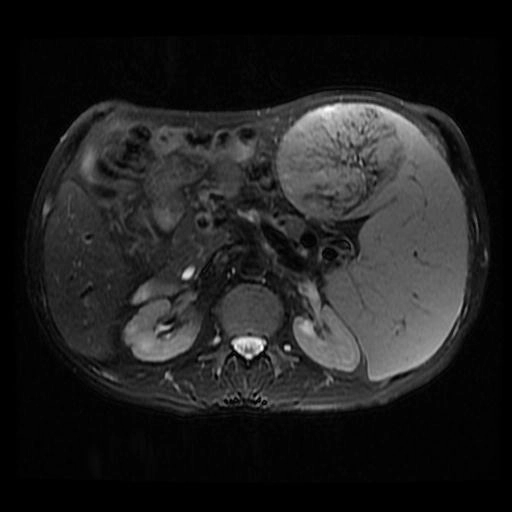

• U mạch máu ác tính lách (Splenic angiosarcoma)